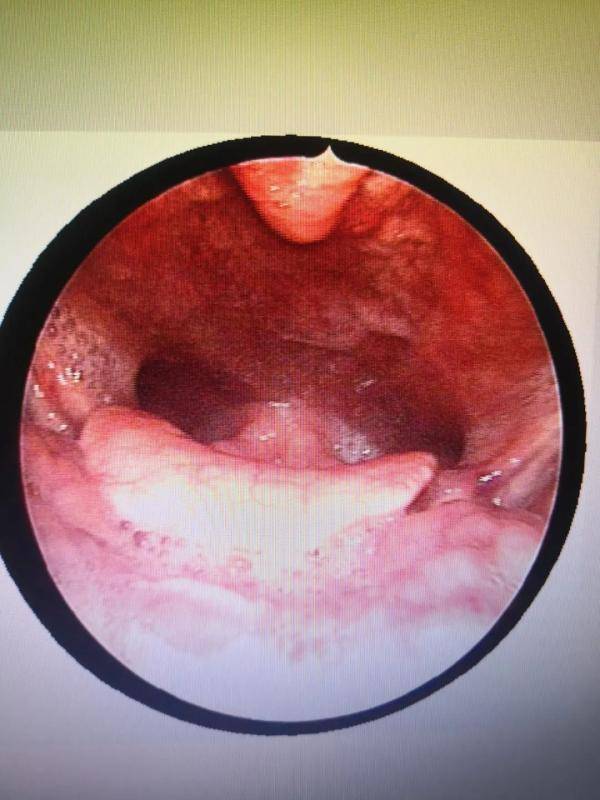

咽喉!扁桃体喉咙两侧有两块肉,肿大,不痛,吞噎有异物感

图片尺寸484x648